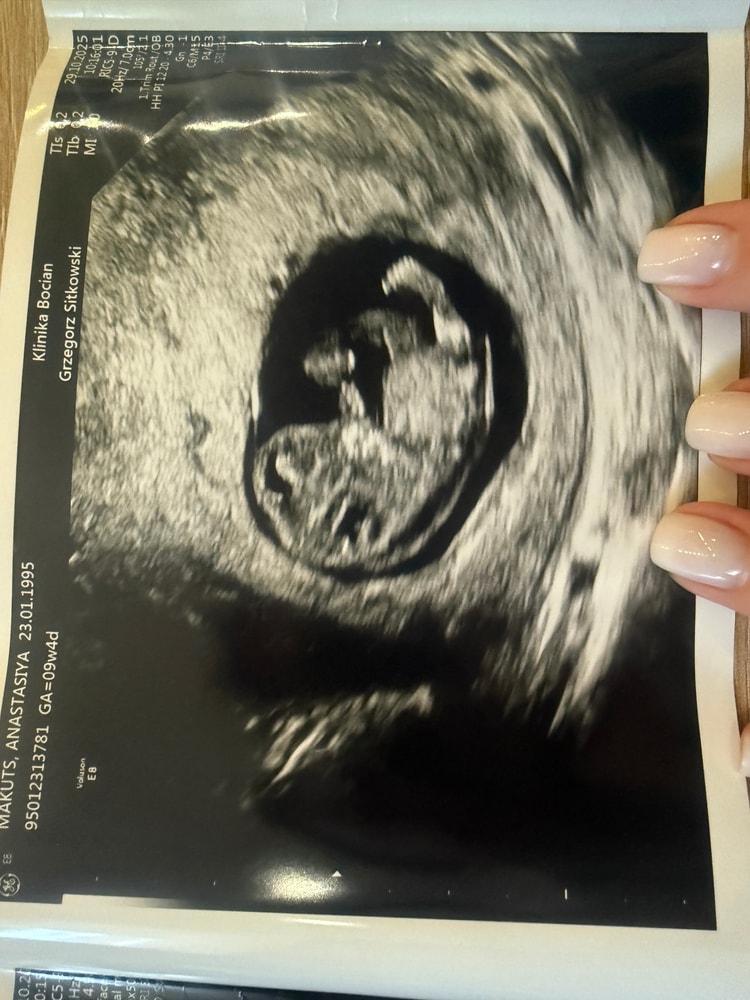

Узи 9 недель и 4 дня

Но когда на УЗИ увидела нашего малыша 😍 — с ручками, ножками, послушали сердечко (171 уд/мин) — он так активно шевелился! Даже не верится, такая кроха — всего 2,9 см, а уже такой большой! Я, конечно, расплакалась от счастья ❤️